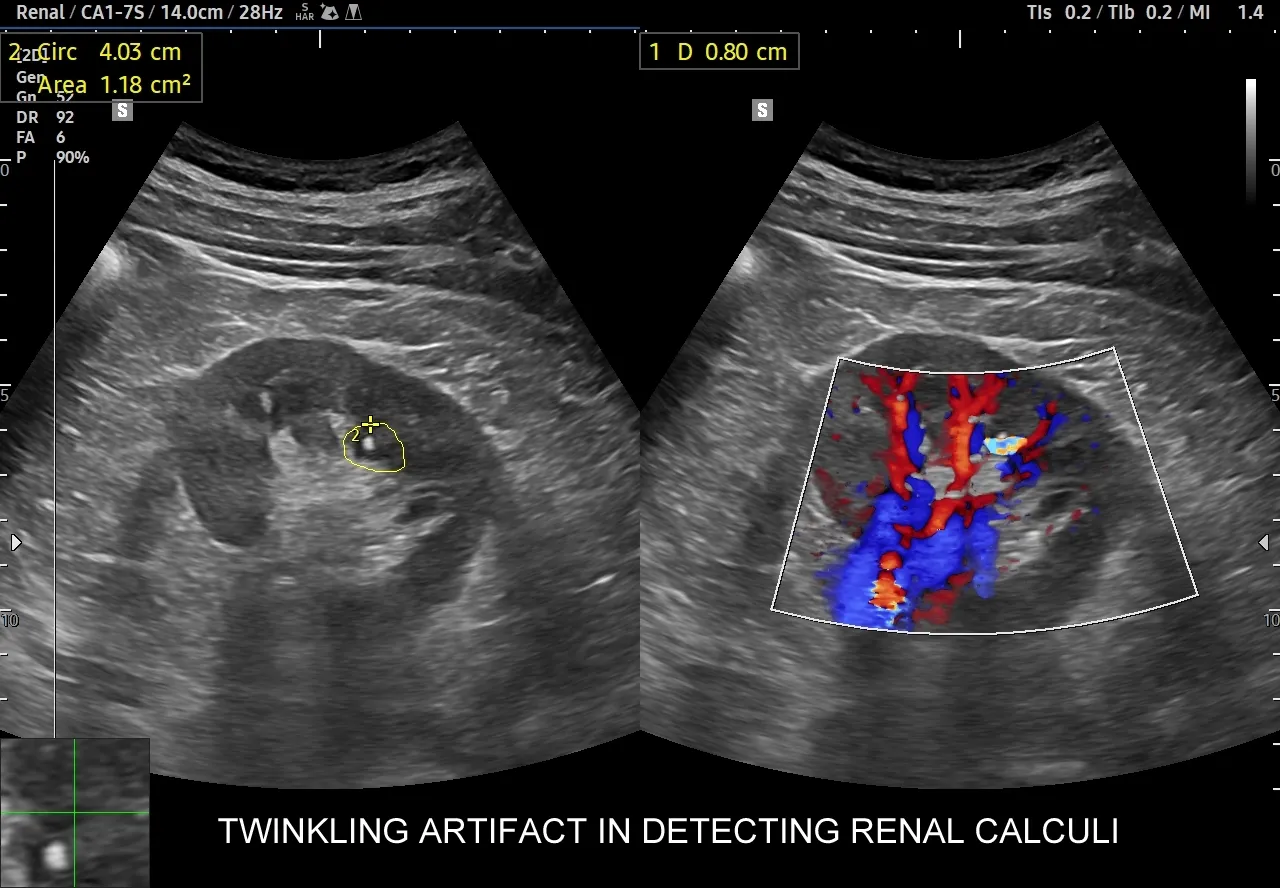

Aby "zajrzeć do środka" i dokładnie ocenić stan nerek, niezbędne są badania obrazowe. Najczęściej zaczynamy od USG układu moczowego. Jest to badanie nieinwazyjne, łatwo dostępne i pozwala szybko ocenić wielkość nerek, obecność kamieni, torbieli, wodonercza czy większych guzów. Jest to doskonałe narzędzie przesiewowe. Jeśli USG nie daje jednoznacznych odpowiedzi lub podejrzewam bardziej złożone problemy, sięgam po bardziej zaawansowane metody. Tomografia komputerowa (TK) jest niezwykle precyzyjna w wykrywaniu kamieni nerkowych, nawet tych bardzo małych, a także w ocenie guzów i zmian strukturalnych. W niektórych przypadkach, zwłaszcza gdy potrzebujemy szczegółowej oceny tkanek miękkich, naczyń krwionośnych lub gdy pacjent nie może być narażony na promieniowanie rentgenowskie (np. kobiety w ciąży), zlecany jest rezonans magnetyczny (MRI). Każde z tych badań ma swoje specyficzne zastosowanie i pomaga mi uzyskać pełny obraz sytuacji, co jest kluczowe dla postawienia trafnej diagnozy i wdrożenia skutecznego leczenia.